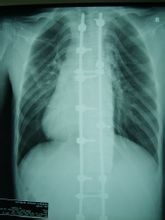

主要有四肢細長,蜘蛛指(趾),雙臂平伸指距大於身長,雙手下垂過膝,上半身比下半身長。長頭畸形、面窄、高齶弓、耳大且低位。皮下脂肪少,肌肉不發達,胸、腹、臂皮膚皺紋。肌張力低,呈無力型體質。韌帶、肌腱及關節囊伸長、鬆弛,關節過度伸展。有時見漏斗胸、雞胸、脊柱後凸、脊柱側凸、脊椎裂等。

約80%的患者伴有先天性心血管畸形。常見主動脈進行性擴張、主動脈瓣關閉不全,由於主動脈中層囊樣壞死而引起的主動脈竇瘤、夾層動脈瘤及破裂。二尖瓣脫垂、二尖瓣關閉不全、三尖瓣關閉不全亦屬本徵重要表現。可合併先天性房間隔缺損、室間隔缺損、法樂氏四聯征、動脈導管未閉、主動脈縮窄等。也可合併各種心律失常如傳導阻滯、預激綜合徵、房顫、房撲等。

馬凡氏綜合徵的主要危害是心血管病變,特別是合併的主動脈瘤,應早期發現,早期治療。根據臨床表現骨骼、眼、心血管改變三主征和家族史即可診斷。臨床上分為兩型:三主征俱全者稱完全型;僅二項者稱不完全型。診斷此病的最簡單手段是超聲心動圖,有懷疑者均可行此檢查,進一步確診則需要通過MRI(磁共振顯像)。目前尚無特效治療。